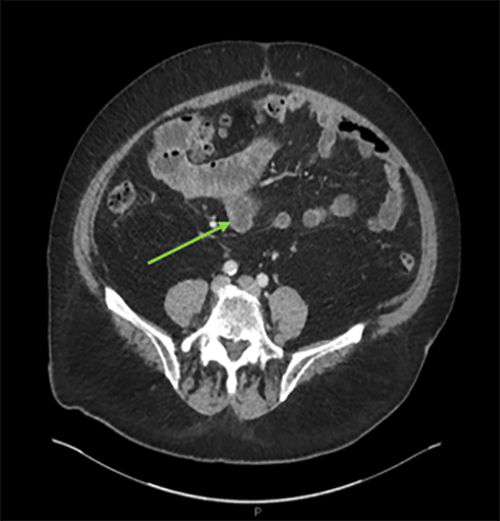

The patient is an 86-year-old male with a history of diastolic heart failure, diabetes mellitus, atrial fibrillation/flutter s/p cardioversion in the past, and coronary artery disease s/p three-vessel coronary artery bypass who presented to our emergency department with three days of persistent, cramping epigastric and periumbilical pain and no other notable symptoms. Vital signs on presentation were normal, but the patient was in atrial flutter. Labs obtained in the ED were notable for a white blood cell count of thirteen thousand. A CT of the abdomen and pelvis with IV contrast was performed and showed a fecalized and blind-ending pouch arising from the distal ileum within the central abdomen with surrounding inflammatory stranding that appeared consistent with an inflamed Meckel’s diverticulum.

Figure 1. ED CT Showing Meckel’s diverticulum. Published With Permission